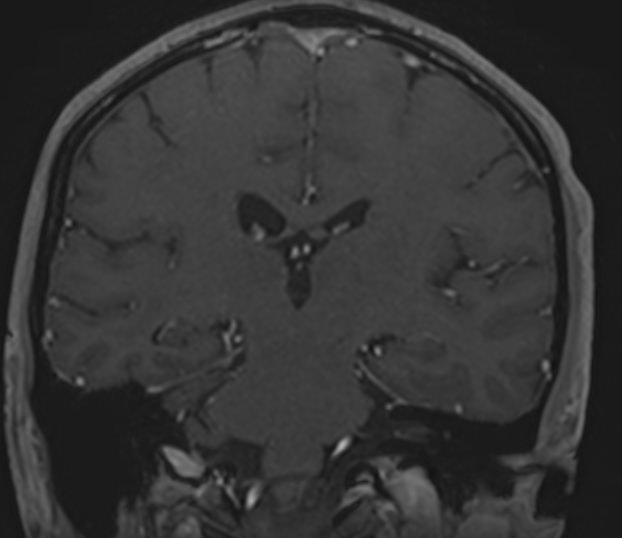

МРТ головного мозга с контрастированием – методика проведения магнитно-резонансной томографии, при которой внутривенно вводится препарат, содержащий гадодиамид (соли металла гадолиния). Контрастное вещество не проникает через гемато-энцефалический барьер и в норме не накапливается в тканях головного мозга. Однако при нарушении его целостности способно накапливаться в патологических очагах, в частности, в опухолях, зонах воспаления и участках демиелинизации нервных волокон.

Это способствует ранней диагностике заболеваний головного мозга, таких как рассеянный склероз, доброкачественные и злокачественные новообразования. Кроме того, с помощью контраста можно оценить степень и характер васкуляризации патологического процесса.

Исследование в нашей клинике выполняется на современном высокопольном томографе экспертного класса TOSHIBA VANTAGE TITAN 1,5 Тесла, который использует разные режимы сканирования с толщиной среза от 1мм в различных плоскостях с последующей цифровой обработкой полученных данных для создания трехмерных изображений. Аппарат позволяет выявлять структурные изменения в веществе головного мозга уже на начальной стадии, когда другие методы не дают результатов.